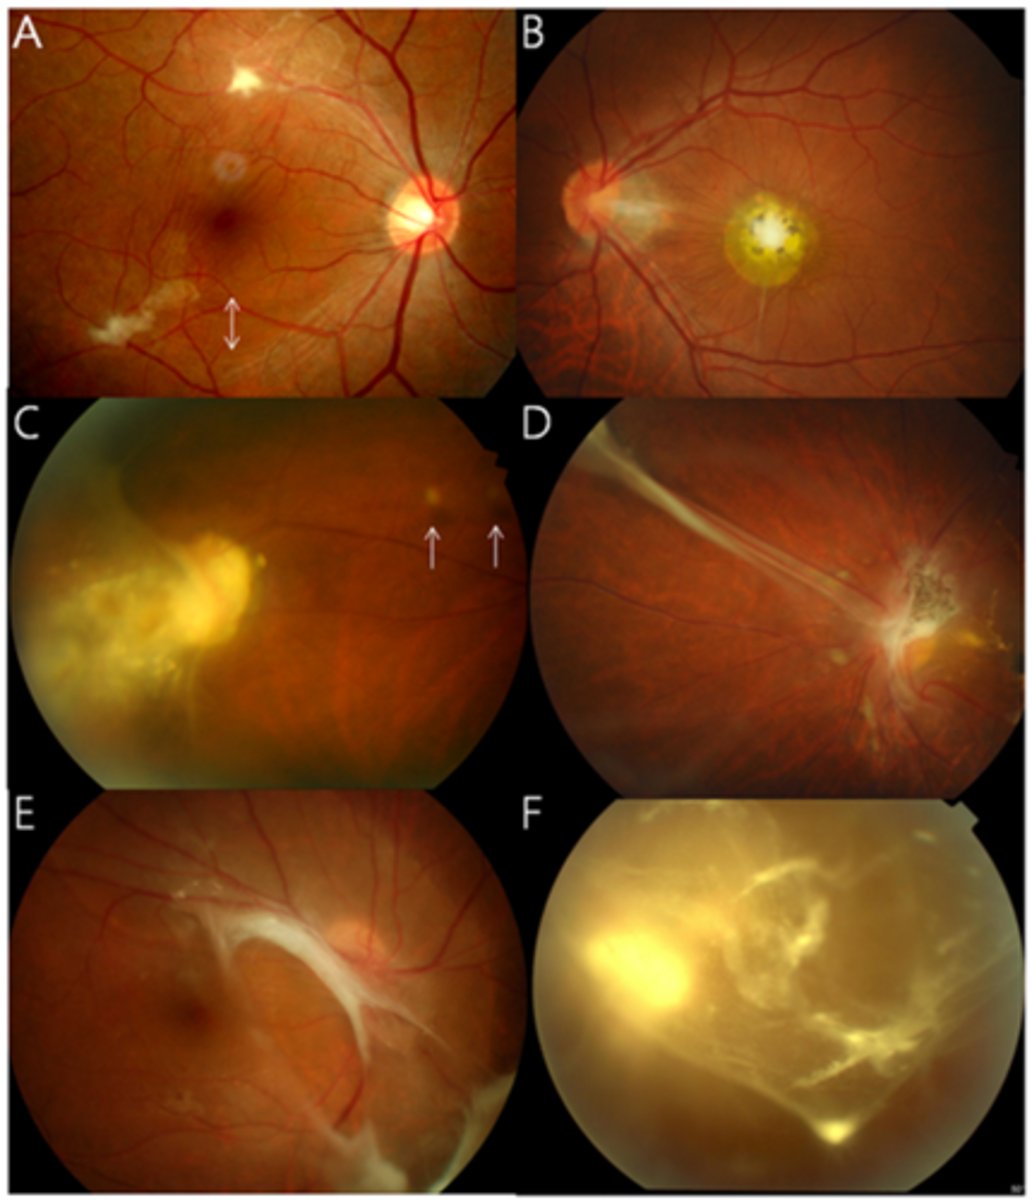

How does choroidal rupture appear on fundoscopy?

curvilinear or crescent-shaped streak, sometimes concentric to ONH

+/- subretinal /subRPE hemorrhage (acute)

Bruch's/Choriocapillaris/RPE damage

overlying neurosensory retina is intact

+/- RPE hyperplasia (chronic)

+/- CNV over time

tesselated or tigroid fundus = visibility of choroidal vasculature (A)

What are some common findings in degenerative myopia?

lattice degeneration

holes/tears

posterior staphyloma

lacquer cracks (C)

myopic retinoschisis

glaucoma

What findings of degenerative myopia are seen here?

PPA

crescent

lacquer cracks

How do lacquer cracks appear on fundoscopy?

jagged, irregular yellow lines showing sclera in the posterior pole

What are angioid streaks and what type of atrophy do they lead to?

breaks in Bruch's membrane in a radiating fashion emanating from the ONH = leads to RPE, PR's, choriocapillaris atrophy